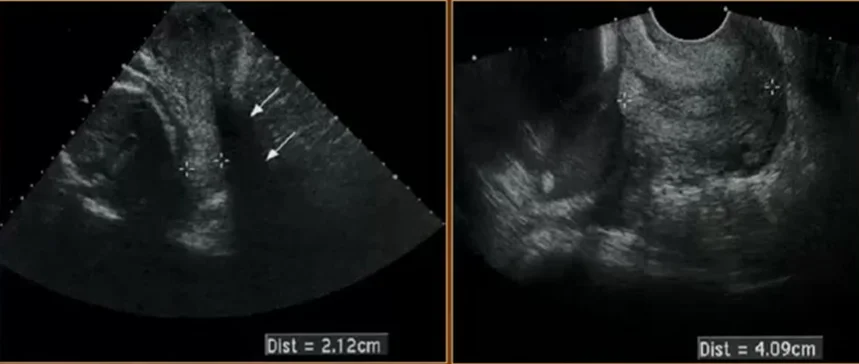

• Hở eo tử cung và cổ tử cung ngắn (Cervical Insufficiency / Short Cervix)